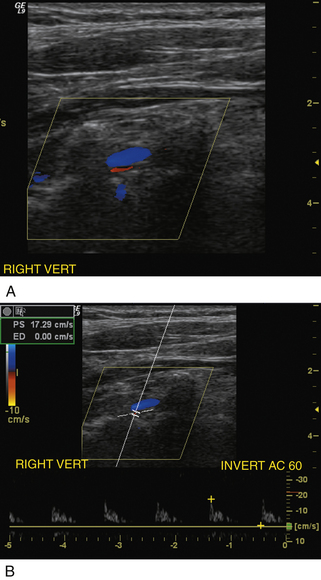

Более распространенной находкой, чем отсутствие кровотока в позвоночной артерии, является обратный кровоток или подключичное обкрадывание. Это простой диагноз, который можно поставить с помощью дуплексного ультразвукового исследования, поскольку ретроградный кровоток в позвоночной артерии наблюдается на протяжении всего сердечного цикла ( рис. 11-10 ), хотя следует соблюдать осторожность, чтобы не спутать сигнал пульсирующего потока в позвоночной вене с обратным потоком в позвоночной артерии. В 90% случаев обратный позвоночный поток (за счет подключичного обкрадывания) возникает с левой стороны. У пациентов с подключичной обкрадой также должна быть возможность документировать аномальные формы скорости кровотока в дистальном сегменте пораженной подключичной артерии ( рис. 11-11 ). При обнаружении реверса позвоночного кровотока с правой стороны важно определить, является ли источником обкрадывания подключичная артерия, которая влияет только на кровоток в позвоночной артерии, или безымянная артерия, оказывающая существенное влияние как на правую общую сонную артерию, так и на безымянную артерию, которая оказывает существенное влияние как на правую общую сонную артерию, так и на и позвоночные артерии. Обычно у пациентов с подключичным обкрадыванием разница систолического давления между нормальной и пораженной руками превышает 15–20 мм рт. ст. Дополнительным признаком может быть увеличение размера позвоночной артерии и сильный компенсаторный кровоток, контрлатеральный подключичному обкраду; Однако из-за большой вариабельности нормального размера позвоночной артерии и скорости кровотока, упомянутой ранее, этот результат не является диагностическим как изолированное наблюдение.

Часто в случаях подключичного обкрадывания может возникнуть обструкция подключичной артерии в ее начале, гемодинамически значимая, но не настолько тяжелая, чтобы вызвать полное изменение кровотока в ипсилатеральной позвоночной артерии. Изменение баланса гемодинамических сил во время сердечного цикла вызывает замедление систолического кровотока в позвоночной артерии ( рис. 11-12 ), которое, если оно достаточно сильное, проявляется как двунаправленный поток ( рис. 11-13 ). Во время пиковой систолы происходит значительное падение давления на стенозе подключичной артерии в связи с высокоскоростной струей потока. В то же время в контралатеральной позвоночной артерии и основной артерии присутствует нормальное систолическое давление. В результате возникает чистый градиент давления от дистального к проксимальному поперек позвоночной артерии на стороне подключичного стеноза, что вызывает замедление во время систолы или даже временное изменение направления кровотока. Во время диастолической фазы сердечного цикла скорость кровотока в пораженной подключичной артерии снижается и значительного падения давления в месте стеноза не происходит; таким образом, во время диастолы чистый градиент давления внутри пораженной позвоночной артерии по существу нормальный и обеспечивает антеградный поток с уменьшенной абсолютной скоростью потока.

РИСУНОК 11-13. Аномалии формы позвоночных волн, ипсилатеральные по отношению к прогрессирующему обкрадению подключичной мышцы. Этот спектральный допплеровский сигнал показывает двунаправленный поток. В этом случае стеноз подключичной артерии достаточно серьезен, чтобы вызвать временное изменение направления кровотока во время пиковой систолы с уменьшенным, но антеградным потоком во время диастолы.